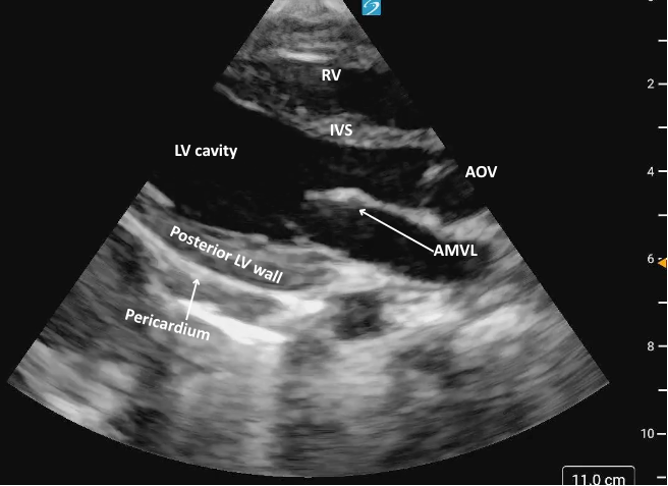

Parasternal Long Axis

In the PLAX view, we see the interventricular septum (IVS), LV cavity, and the posterior wall of the LV (Figure 3). You should see the mitral valve, LV outflow tract, and AOV in one continuous plane. Most often, you will not see the distal ventricle/apex in the same window as your AOV/MV.

Foreshortening is a common limitation to the PLAX view, and recognizing when you are foreshortened is important to avoid overestimating systolic function. Signs of foreshortening include a LV cavity that seems unusually short and truncated, rather than elongated (figure 4). Remember to ensure that you have the AMVL as well as the point of coaptation of the AOV cusps clearly visible in the same plane and the ventricle looks elongated an bullet shaped as this will ensure that you are in the true long-axis position and will avoid the risk of foreshortening.

Figure 3: Parasternal long axis view in cardiology convention anatomically labeled.